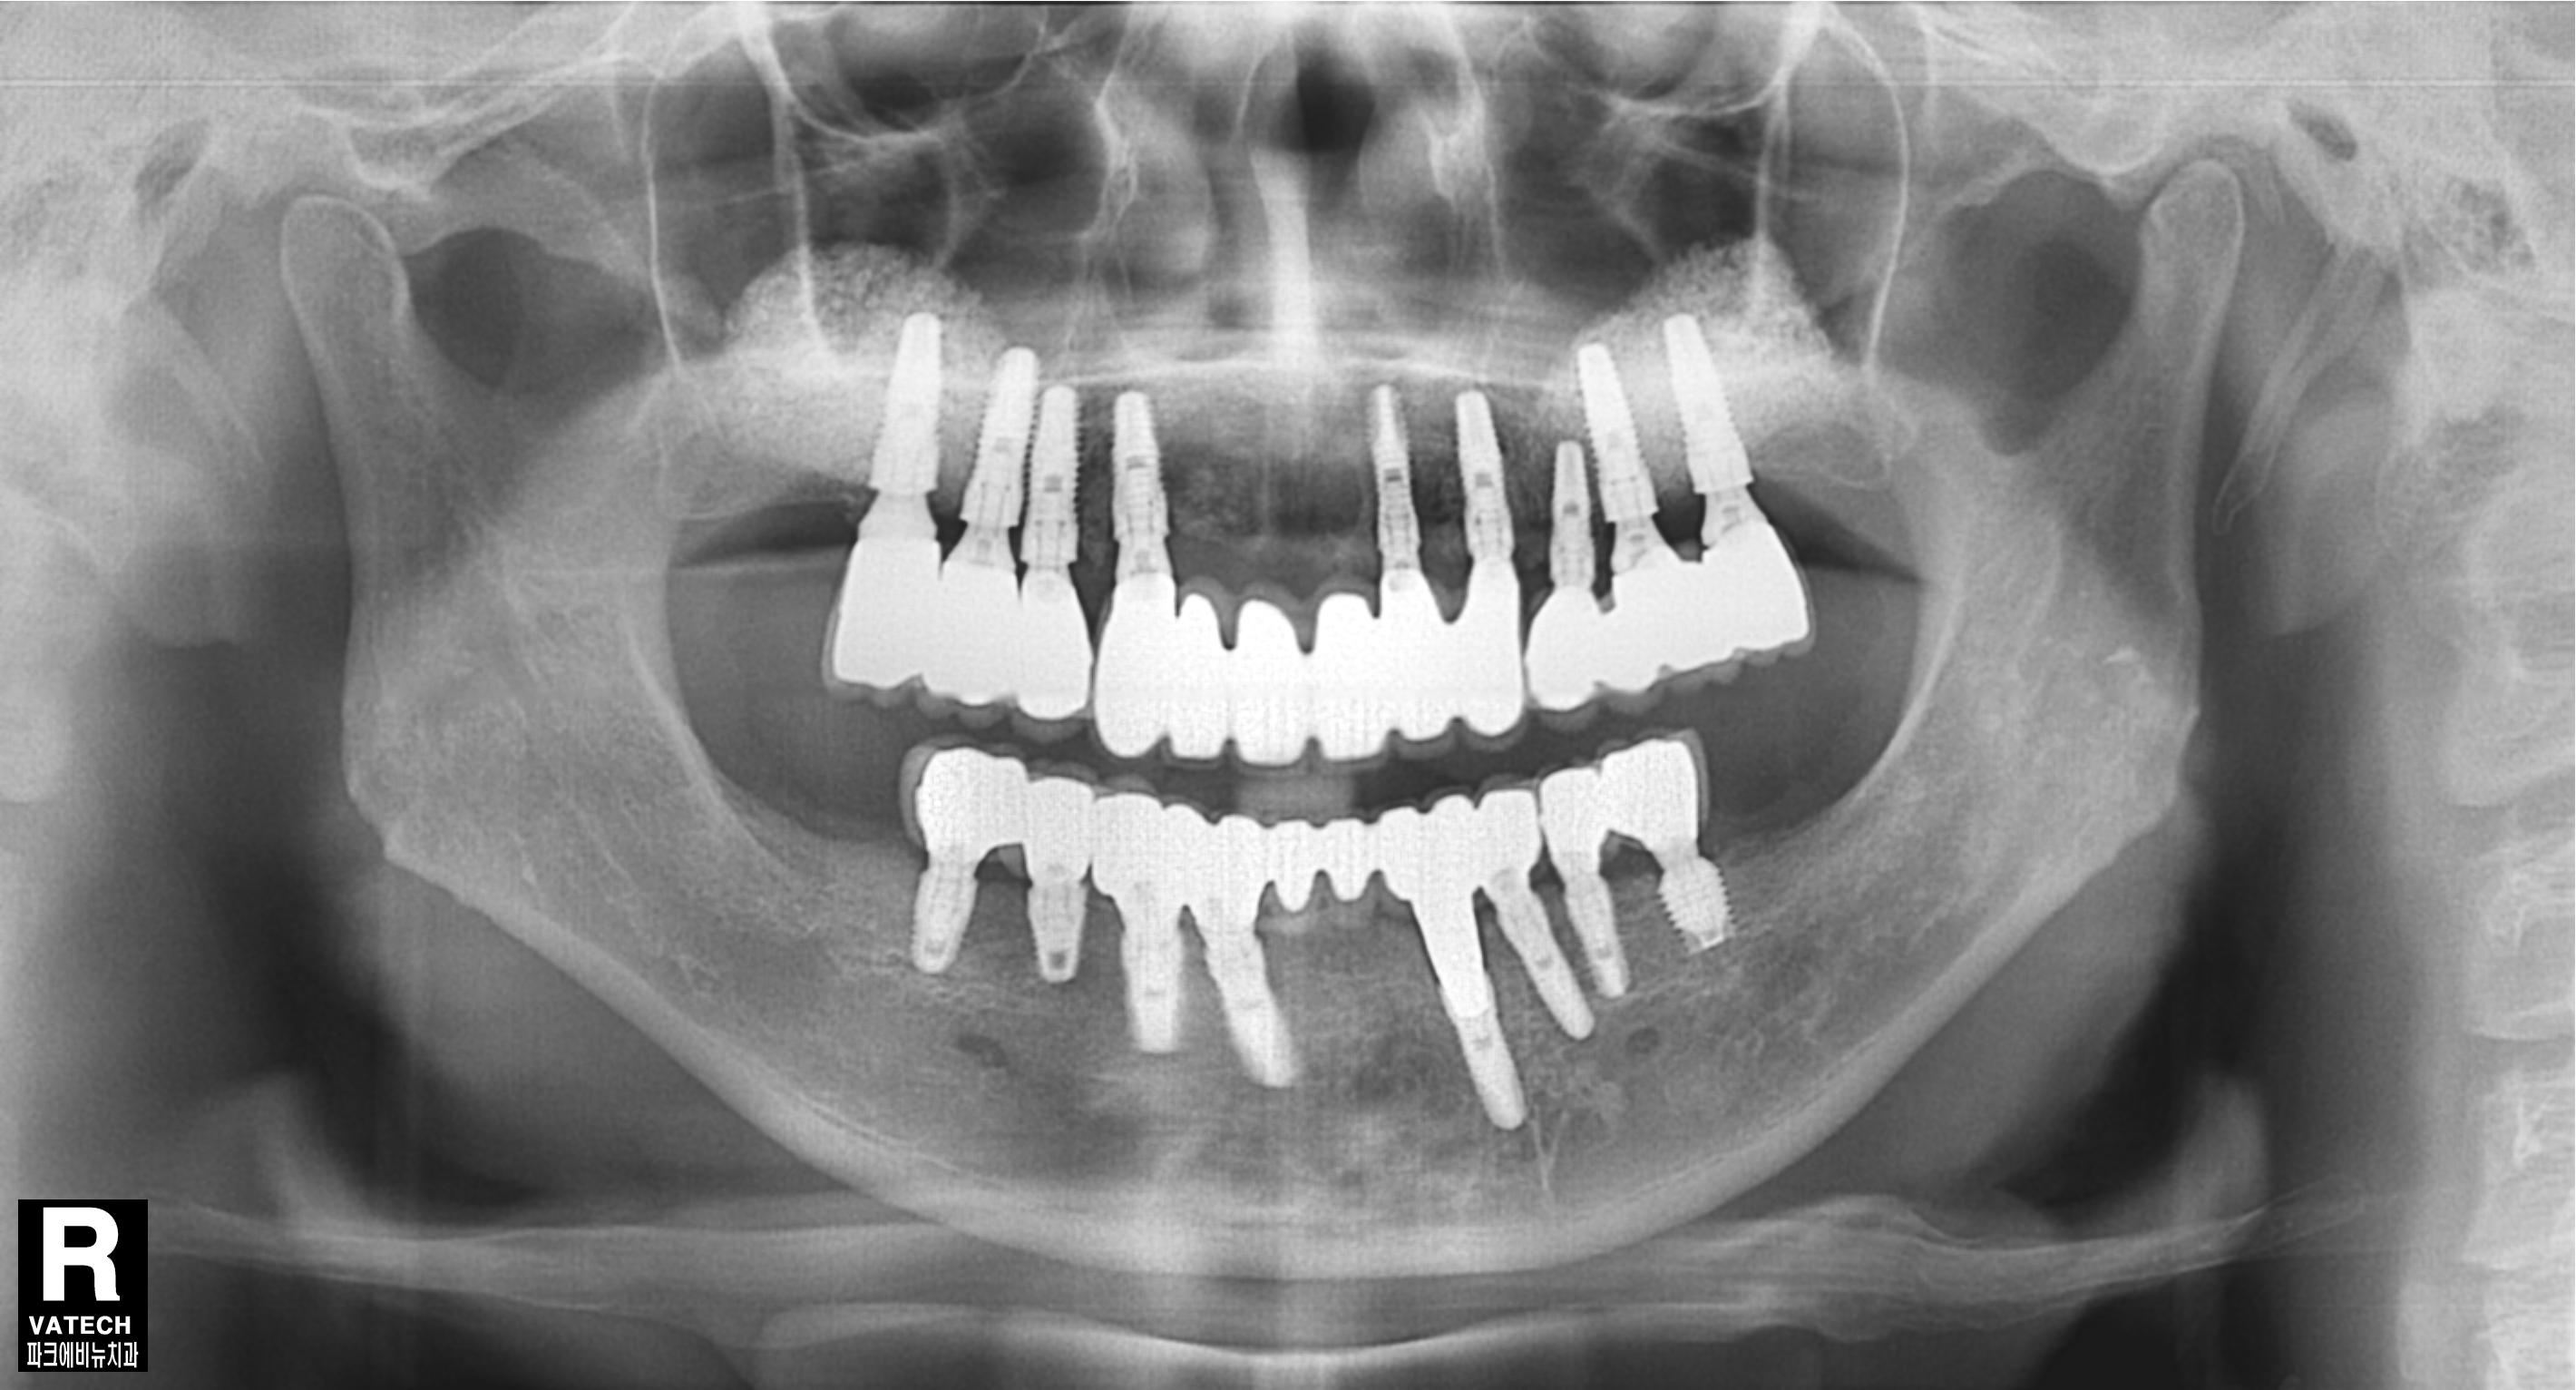

파노라마 방사선 사진도 살펴보면 치아를 잡는 치조골이 치아 뿌리 끝까지 많이 녹았음 확인할 수 있었습니다.

따라서 치아를 발치하고 전악 임플란트를 수복하기로 결정 하였습니다.

치료 중 찍은 방사선 사진입니다.

치료 필요에 따라 뼈이식도 진행하였습니다.